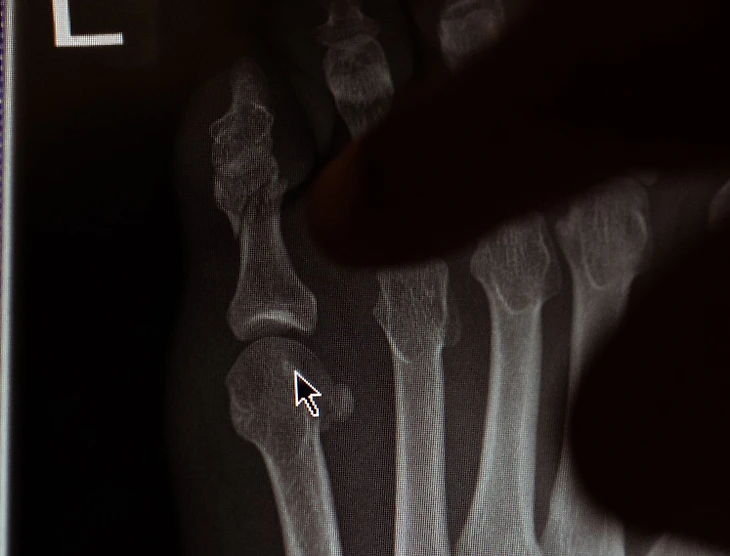

Конор ответил Сонену, что травмировал мизинец, и приложил фотографии снимков. Позже Конор выложил большой пост с объяснениями:

«Мы были так готовы к бою, что это просто выбивает из колеи. Я хочу новую Bugatti. Как мне оправдываться, что получу ее сейчас без этих боев? Мы потеряли концентрацию и провели тренировку, не надев полную защитную экипировку, поэтому я ударился мизинцем и сломал палец. Нужно несколько недель – и все.